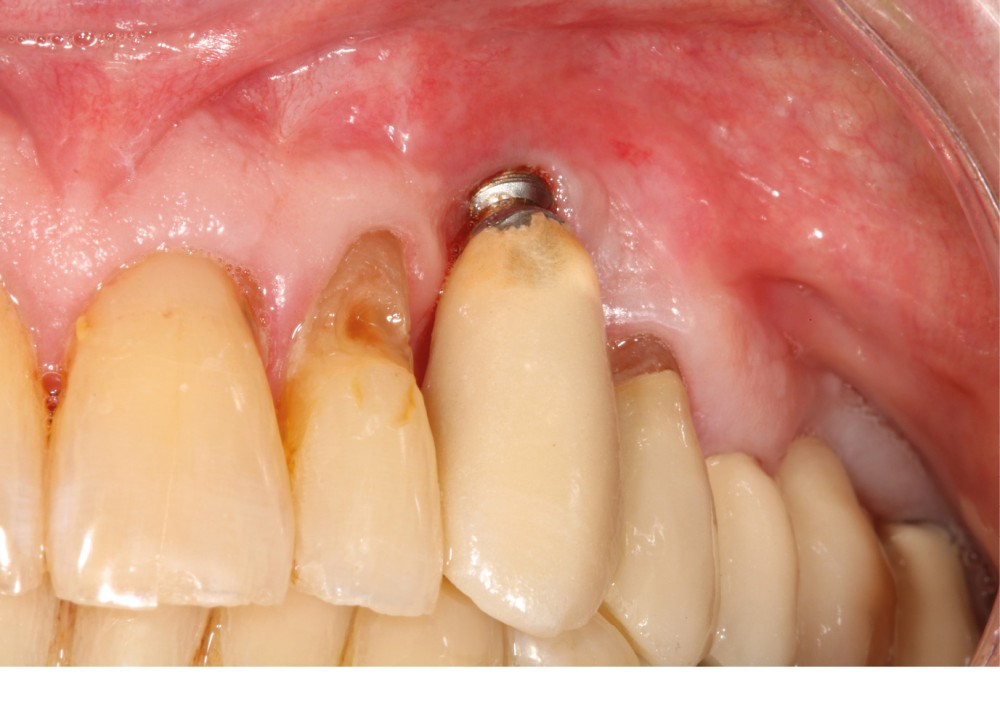

Le patient

- 70 ans

- Pas d’antécédents médicaux

- Ne fume pas

- Hygiène correcte

L’implant

- Site 23

- Mis en place il y a 12 ans